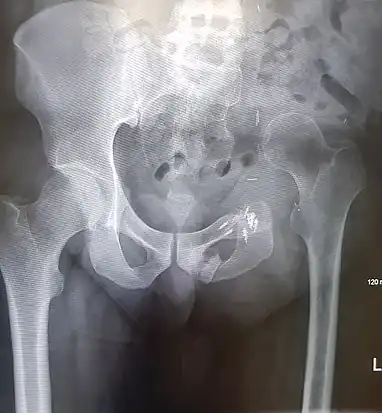

An x-ray of a limb-sparing hemipelvectomy on the left side of a male pelvis taken one month after surgery. An x-ray of a limb-sparing hemipelvectomy on the left side of a male pelvis taken one month after surgery.

An x-ray of the same pelvis taken eighteen months after surgery highlighting the femur migration to its final resting place. An x-ray of the same pelvis taken eighteen months after surgery highlighting the femur migration to its final resting place.